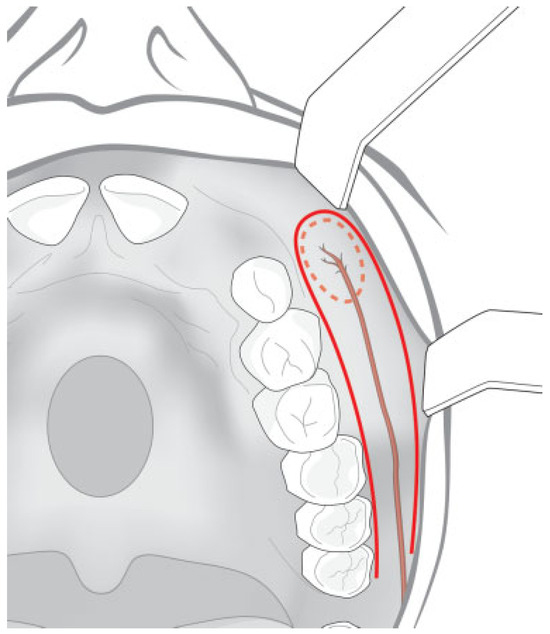

Posteriorly Based Flap

The length of the skin component of the flap is the distance between the most anterior and posterior point of the nasal mucosa defect. The length of the muscle mucosa component in the posteriorly based flap is the same as the distance from the most anterior point of the oral mucosa defect to the pivot point. The pivot point in this case is located behind the maxillary arch (retromolar trigone). The lateral nasal artery is identified and divided at the distal border of the flap and distal to the cutaneous perforator.

A main perforator is located a few millimeters before the distal division of the lateral nasal artery (below the alar base) and can be used in posteriorly based flap (Figure 2). This perforator should not be dissected to avoid its injury, and the subcutaneous tissue is dissected around it in connection with the skin island and the musculomucosal component of the flap. The skin island is located over the nasolabial fold and below the alar base.

Figure 4. Diagram showing the inferiorly based nasal artery myomucosal cutaneous flap for palatal fistula repair.

Figure 19. Posteriorly based nasal artery musculomucosal cutaneous flap.